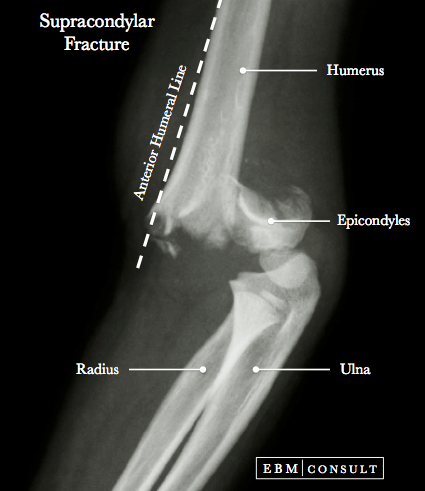

Explanation: The median nerve runs anterior to the elbow joint through the cubital fossa, making it vulnerable in supracondylar humerus fractures. This may lead to loss of forearm flexors and thenar muscle function as well as hand of benediction when trying to make a fist

A) is incorrect because the ulnar nerve runs behind the medial epicondyle.

B) is incorrect because the radial nerve runs posteriorly in the radial groove.

D) is incorrect since the musculocutaneous nerve lies in the arm, not at the elbow.

E) is incorrect because the axillary nerve is at the surgical neck, not the distal humerus.